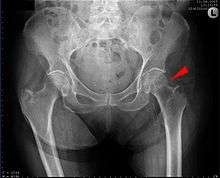

AP hip radiograph demonstrating an intertrochanteric fracture

Intertrochanteric hip fracture in a 17-year-old male

Medial fracture in a 92-year-old woman

X-rays of the affected hip usually make the diagnosis obvious; AP (anteroposterior) and lateral views should be obtained.